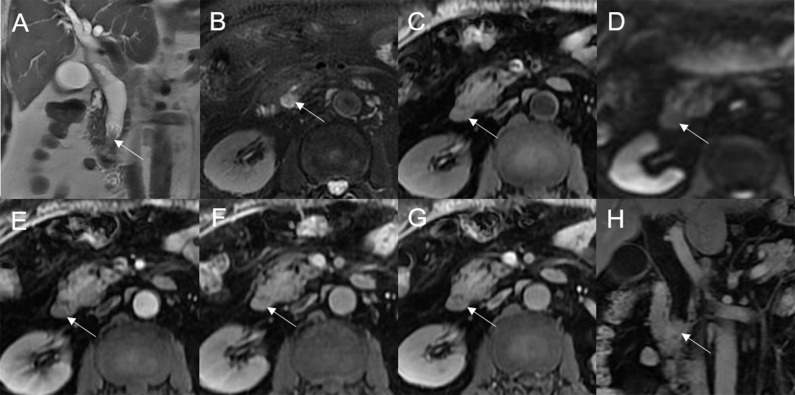

Mean lesion size in the whole sample was 30.83 ± 20.93 mm. All patients presented with an intraluminal ductal mass. While 14/32 (43.75%) lesions presented morphologically as focal eccentric-type masses (f3), 9/32 (28.13%) presented as plaque-like masses, 4/32 (12.50%) as bile duct casting masses, and 5/32 (15.62%) as infiltrative masses. In addition, 8/32 (21.88%) lesions showed a frond-like superficial appearance accompanied by other morphologically categorized appearances other than plaque-like superficial (f4, f5; T2).

Bile duct dilatation upstream of the lesion was present in all cases. Bile duct dilatation downstream of the lesion was present in 6/32 (18.75%) cases (f6) and at the lesion in 24/32 (75%) cases. In 8/32 (25%) cases, there was a stricture in the bile duct lumen at the lesion, along with an enlarged bile duct diameter; while four were cases of bile duct casting masses, the other four were cases of plaque-like masses.

On standard MRI scanning, 24/32 (75%) lesions showed hyperintensity and 9/32 (25%) showed isointensity on T2WI, while 9/32 (28.12%) lesions showed isointensity and 23/32 (71.88%) showed hyperintensity on T1WI. In addition, 3/32 (9.38%) lesions showed speckled hyperintensity on T1WI (f7).

On dynamic enhanced MRI, 14/18 (77.78%) lesions showed moderate enhancement, 2/18 (11.11%) showed obvious enhancement, and 2/18 (11.11%) showed slight enhancement. While 13/18 (72.22%) lesions showed stable and persistent enhancement, 5/18 (27.78%) showed wash-in and wash-out enhancement (T2).

On DWI (b = 800 s·mm-2), 5/32 (15.63%) adenomas showed isointensity (f2) and 27/32 (84.37%) showed hyperintensity. In 2/32 (6.25%) cases, the bile duct wall around the lesion showed hyperintensity on DWI (f8). The mean ADC value of the lesions was 1.65 ± 0.38 × 10-3 mm2·s-1 (T2).

In a previous imaging-based study, 60% of patients with extrahepatic bile duct adenoma had bile duct dilatation (ref. 11); however, the authors did not provide a detailed description of features of the dilated duct. In this study, bile duct dilatation was seen upstream of the lesion in all cases; while dilatation at the lesion site was common, dilatation downstream of the lesion was seen in only a few cases. Among the six cases with downstream bile duct dilatation, two lesions were secreting mucus with a doughy or jelly-like consistency, which may have blocked the distal bile duct. There have been previous reports of this phenomenon in patients with IPNB but not in patients with bile duct adenoma (ref. 19). Four of the six cases of downstream dilatation were in patients with multiple adenomas, with the dilatation being due to blockage of the bile duct by the distal lesion. Stricture of the bile duct lumen at the lesion site, with overall increase in bile duct diameter and upstream dilatation, was seen in all cases of bile duct casting masses and several cases of plaque-like masses. As mentioned earlier, in cases of plaque-like masses, bile duct dilatation at the lesion site was because of duct obstruction by lesions or secretions downstream.